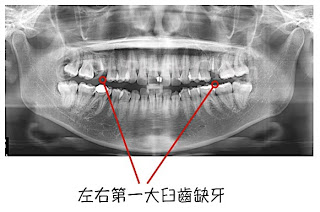

一年多前有個女生來找我,主要是想改善上顎突出 ( maxillary protrusion ) 的問題,同時她也覺得下巴後縮,她說如果手術可以一起改善那就更好了,我告訴她利用適當的手術設計,應該可以一起改善,後來她又提到上排大臼齒有兩顆缺牙,如果手術可以一起改善就完美了。

我告訴她牙齒排列的部分需要和矯正醫師討論,如果適合,是可以利用多片式切骨手術 ( Multi-segmental Osteotomy ) 將上排缺牙空間利用手術關閉,縮短矯正時間。